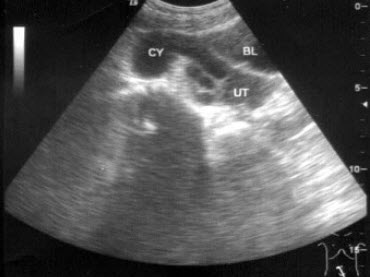

26、单项选择题

女,27岁,下腹部疼痛数月,体检:右侧附件区增厚、增大,B超检查如图所示,最可能的诊断为()

A.右侧卵巢囊肿

B.右侧输尿管扩张

C.右侧输卵管积液

D.盆腔积液

E.以上都不是